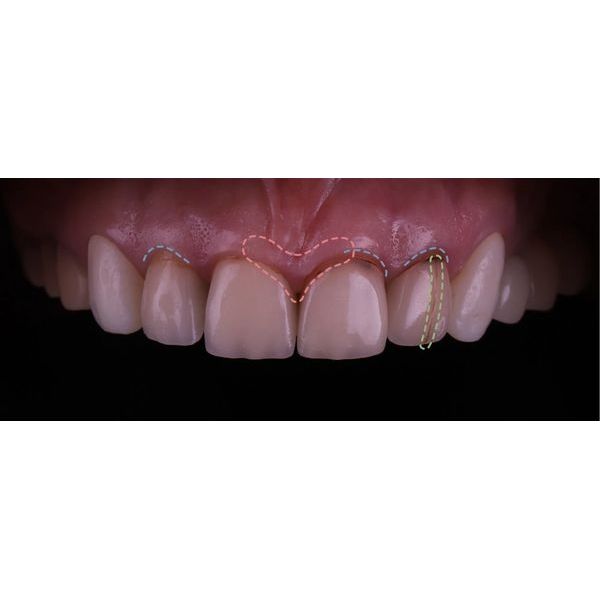

При осмотре выяснилось, что конструкции на центральных зубах хоть и выглядели эстетично, на них появились трещины и сколы, было нарушено краевое прилегание. Кроме того, у женщины наблюдалась стираемость зубов, особенно заметно стёрся нижний клык (зуб 3.3). На других зубах также присутствовали сколы.

Десневой контур был неровным, а сама десна в ряде участков выглядела нездоровой, что могло быть вызвано краевым прилеганием конструкций и неидеальной гигиеной.

- выровняли десневой контур;